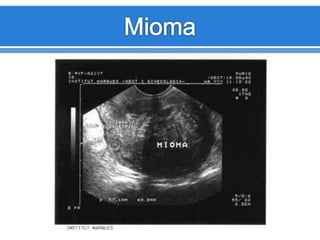

Leiomiomatosis

Los Leomiomas son

tumores benignos

formados por

músculo liso y tejido

conectivo.

Frecuencia de 20%

mujeres > 35 años

Son estrógeno

dependientes

Son múltiples o

únicos

Aspecto

variable.

Útero puede

estar

aumentado

de tamaño.

Hipoecogénicos.

Ecopatrón

Heterogéneo.

Atenuación

acústica o

sombra

acústica

posterior, sin

evidencia de

masa.

FIBROIDES UTERINOS

SUBSEROSO INTRAMURAL SUBMUCOSO

CON CALCIFICACION